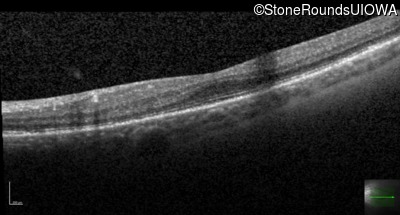

This 16 year old male had an untreatable retinal detachment discovered in his right eye at age 3. A year later he developed a retinal detachment in his left eye which was successfully repaired with a combination vitrectomy and scleral buckle. The visual acuity gradually improved to 20/30 following surgery.

Age at visit: 15 years